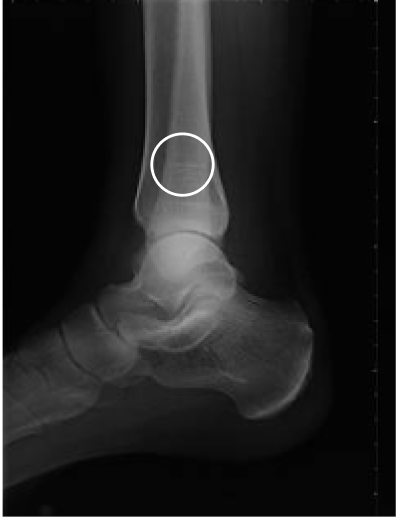

Femur fracture

age 13

Tibial fracture

age 57